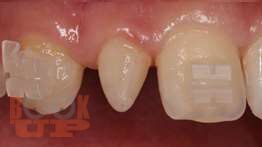

В пособии представлены вопросы этиологии, клиники, диагностики, лечения зубочелюстных аномалий и методы их комплексной профилактики.

Включает в себя тему изменений в околозубных тканях в процессе ортодонтического лечения, описаны ортодонтичекие силы, различные теории перестройки костной ткани, изменения в ВНЧС при перемещениях нижней челюсти. Описаны причины рецидивов как таковых, так и отдельных нозологических форм зубочелюстных аномалий, а так же рекомендации для надежного ретенционного периода и уменьшению рисков возникновения рецидива. Учебное пособие предназначено для студентов, обучающихся по специальности 31.05.03 «Стоматология».